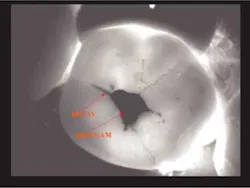

Many may say the above DIFOTI image (Fig. 2) only demonstrates stained fissures. The explorer would not enter the fissures at all. The DIFOTI diagnosis was confirmed with a Diagnodent reading in excess of 70. The tooth was restored in a minimally invasive fashion.

Recurrent caries is difficult to diagnose around an existing amalgam using radiographs. An occlusal DIFOTI image (Fig. 3) will demonstrate recurrent caries around an existing dental restoration.